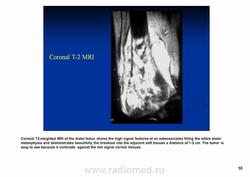

Остеосаркома